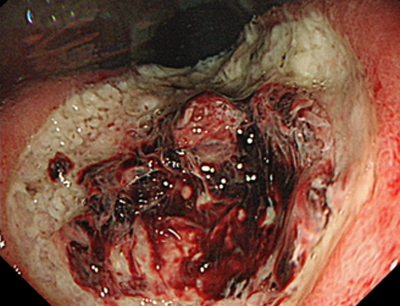

Класифікація NICE (NBI International Colorectal Endoscopic) базується на вузькосмугових зображеннях поліпів товстої кишки. Класифікація враховує забарвлення, судинний малюнок…